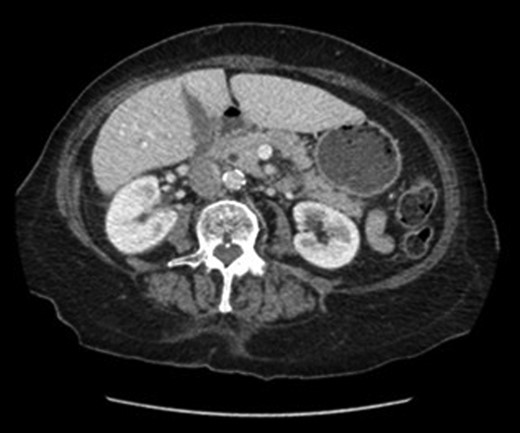

An abdominal ultrasound (Fig. 1) demonstrated a distended gallbladder with multiple subcentimeter gallstones. There was diffuse gallbladder wall thickening up to 7 mm and associated probe tenderness, consistent with cholecystitis. The common bile duct diameter measured up to 7.4 mm without any evidence of choledocholithiasis, thus did not require ERCP. However, the pancreas was not well visualized. A follow-up CT abdomen (Fig. 2) was performed, which demonstrated evidence of pancreatitis with moderate peripancreatic fat stranding without any features of complications including necrosis, abscess or pseudocyst.